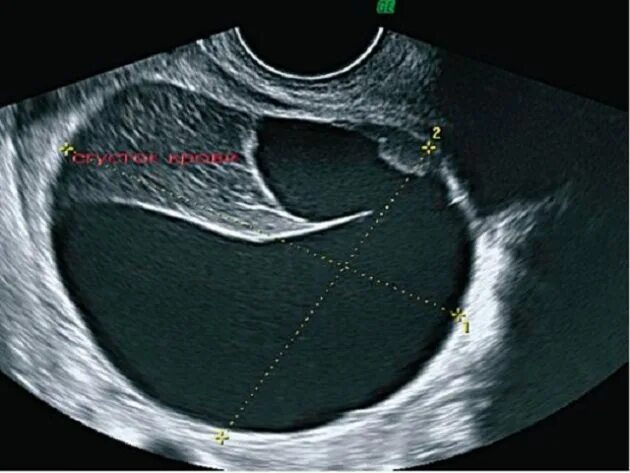

Фолликул 18 мм